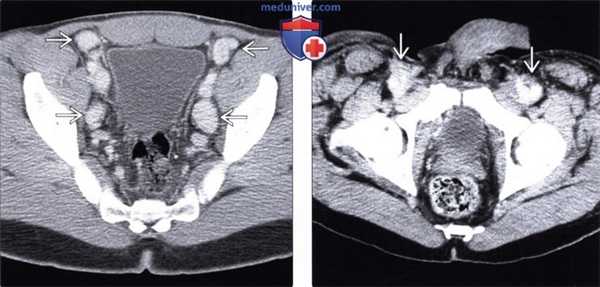

(Слева) На аксиальном КТ срезе таза с контрастным усилением у пациента со СПИДом определяются множественные увеличенные лимфоузлы, интенсивно накапливающие контраст. При эксцизионной биопсии обнаруживаются признаки болезни Кастлемана и СК, которые одинаково могут проявляться выраженным контрастным усилением лимфоузлов.

(Справа) На аксиальной КТ с контрастом у ВИЧ-инфицированного пациента с СК определяется распространенная лимфаденопатия, в т.ч. усиливающиеся при контрастировании лимфоузлы в паховой области. Этот пациент предъявлял жалобы на массивный отек нижних конечностей, что является частым симптомом при паховой лимфаденопатии, обусловленной СК.